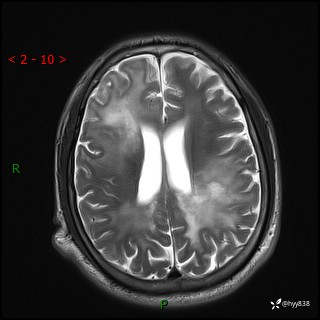

辅助检查:MRI

MRI T2WI